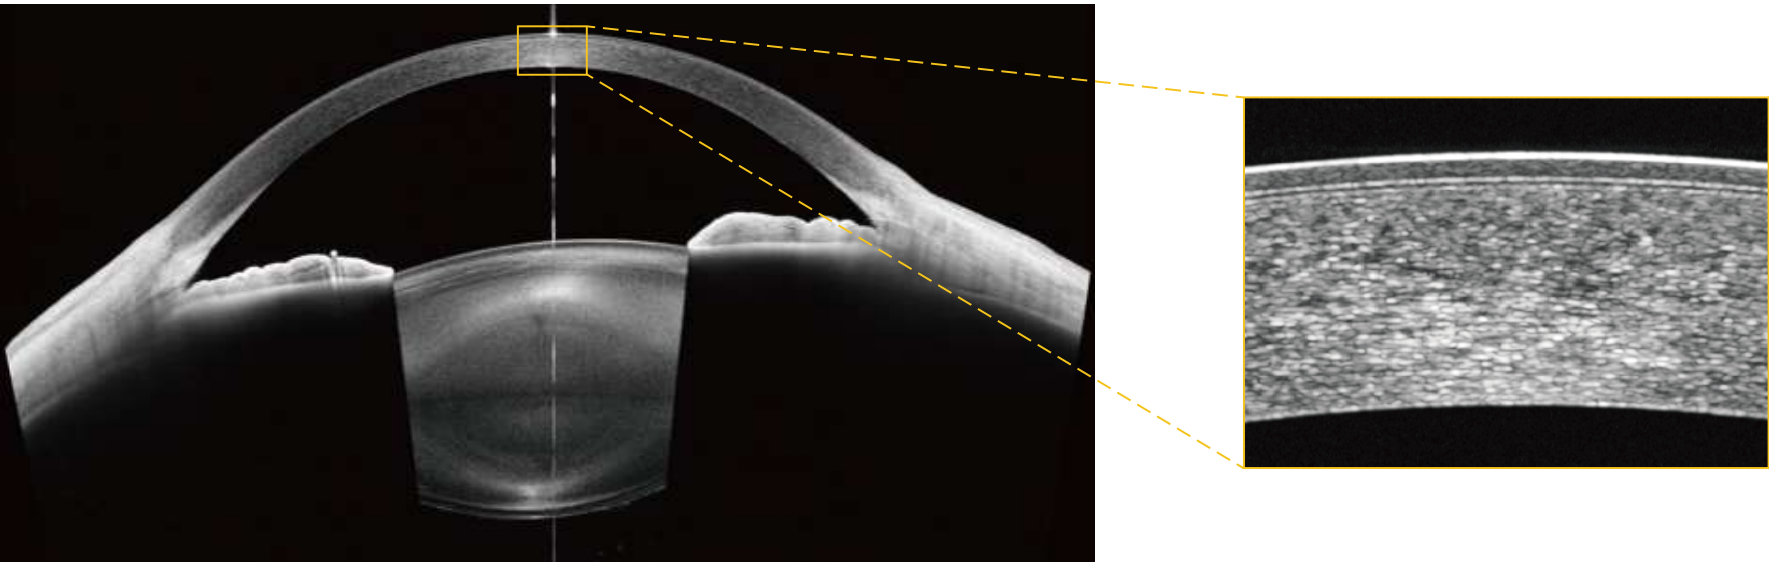

SuperDepth

SuperDepth™ for Full-Depth Visualization

Deep scan range supports broader structural assessment — helping visualize anatomy across depth for retina and anterior segment applications.

One lens

One Lens for Whole-Eye OCT

One platform covers anterior and posterior segment OCT for full eye evaluation.

Vault measurement

Automated ICL Vault Measurement

Automated vault assessment supports safer phakic IOL follow-up in routine practice.